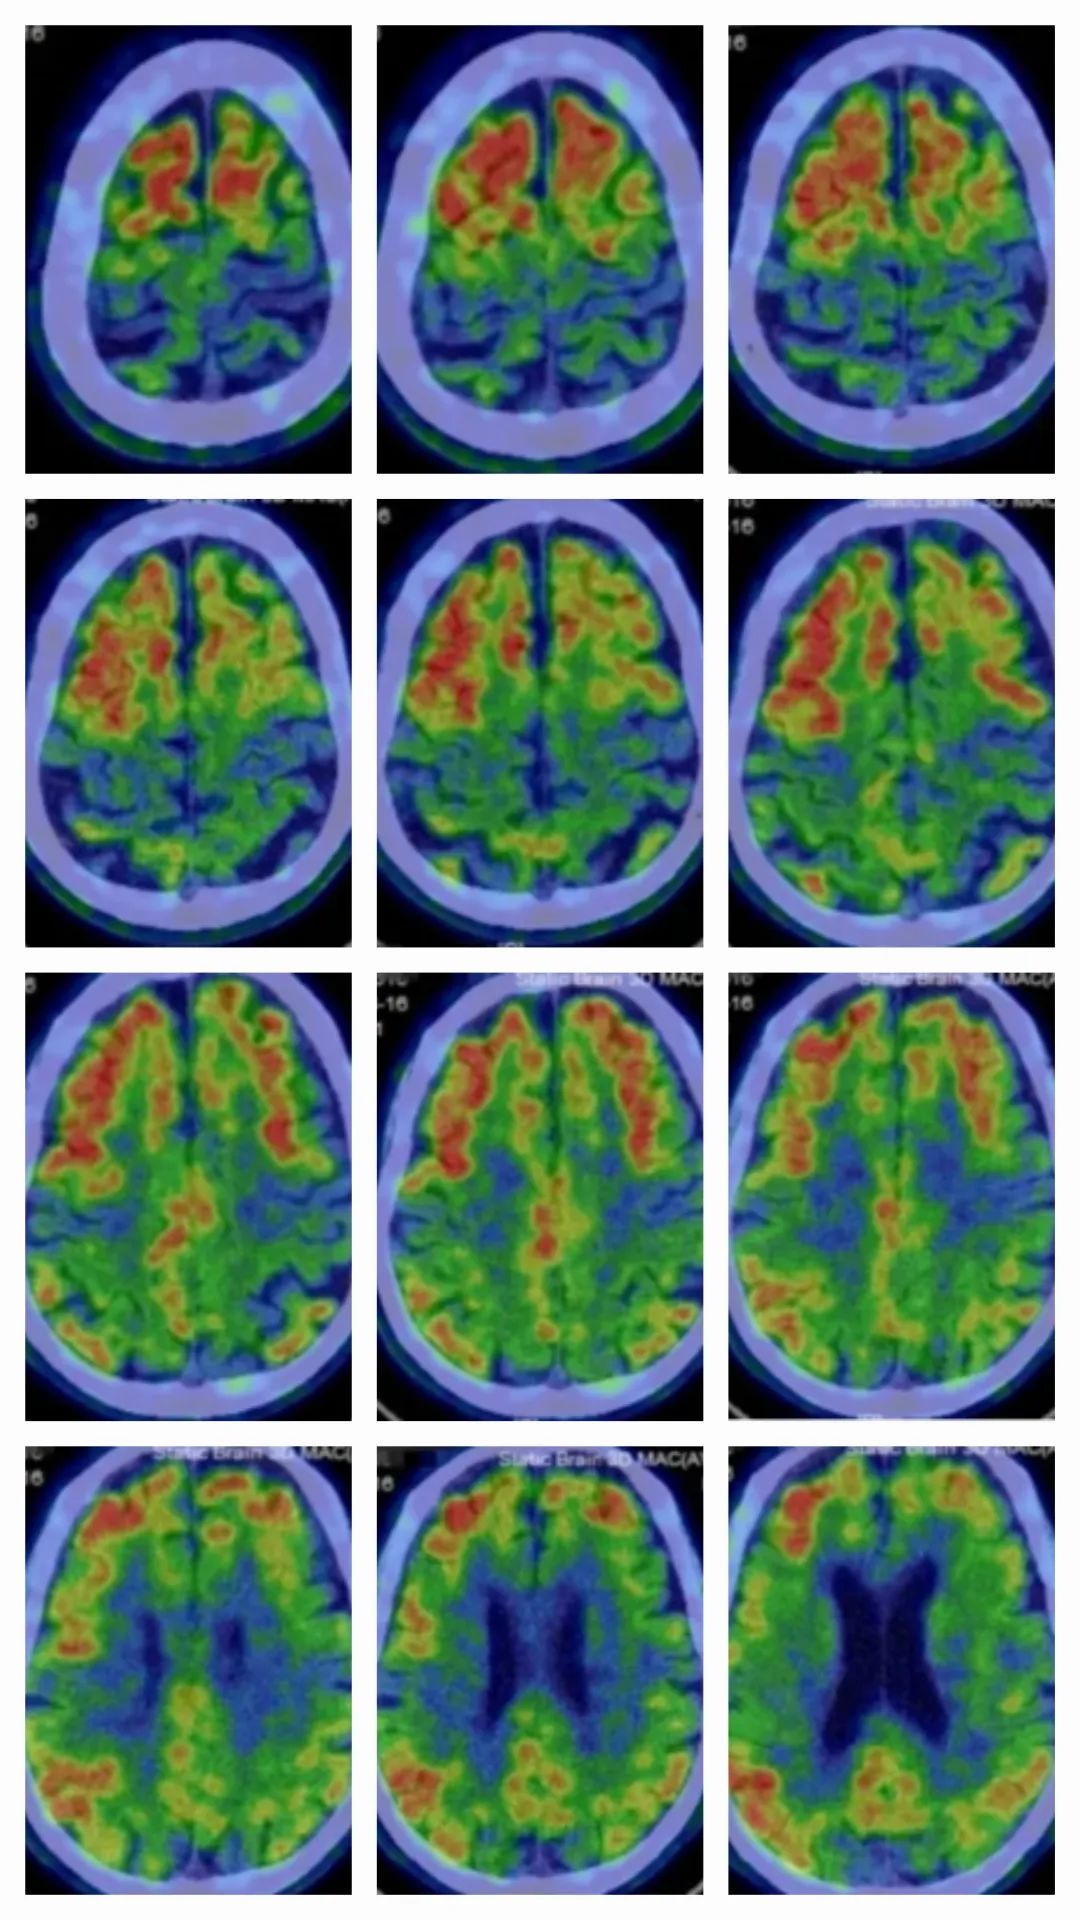

该会诊进一步通过PET-CT淀粉样卵白显像(露馅β淀粉样卵白千里积)效果得到考据。

▲PET-CT露馅张先生脑内存在β淀粉样卵白千里积(图中红色部分)